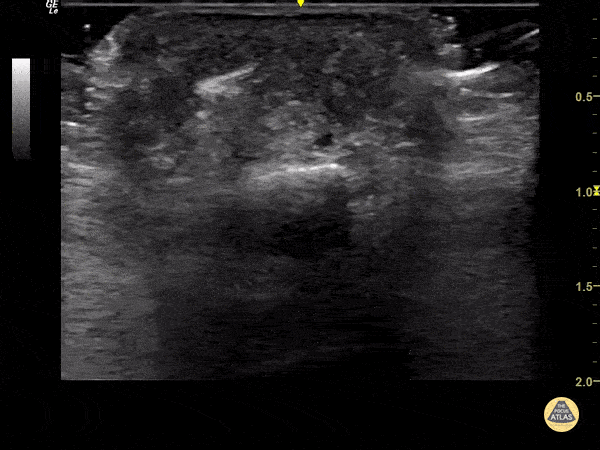

Soft Tissue - Foreign Body Flexor Tendon Sheath

65 year old female with pain and swelling over 4th phalanx, no history of trauma. Hyperechoic density located above flexor tendon sheath. Patient sent to Ortho for surgical exploration. Dr. Magner